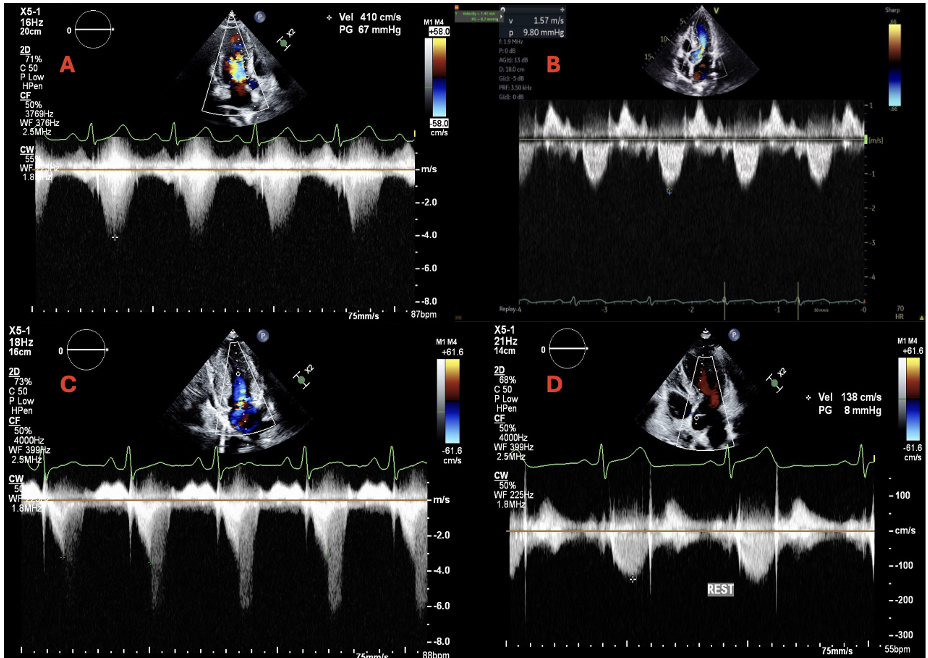

This is a case of a 27-year-old woman with HoCM who was treated with Metoprolol and Mavacamten for 20 months, reducing her LVOT gradient from 70 mmHg to 9 mmHg at rest (Figure 1A and 1B). Despite oral contraceptive use, she had an unplanned pregnancy and immediately discontinued therapy due to teratogenicity concerns.

One month later, the wall motion abnormalities resolved and her LVOT gradient at rest was 51 mmHg (Figure 1C) and Mavacamten was resumed at 5 mg daily, and a non-hormonal intrauterine device was placed. Three months later, her LVOT gradient improved to 8 mmHg at rest (Figure 1D), and reported no functional limitations.